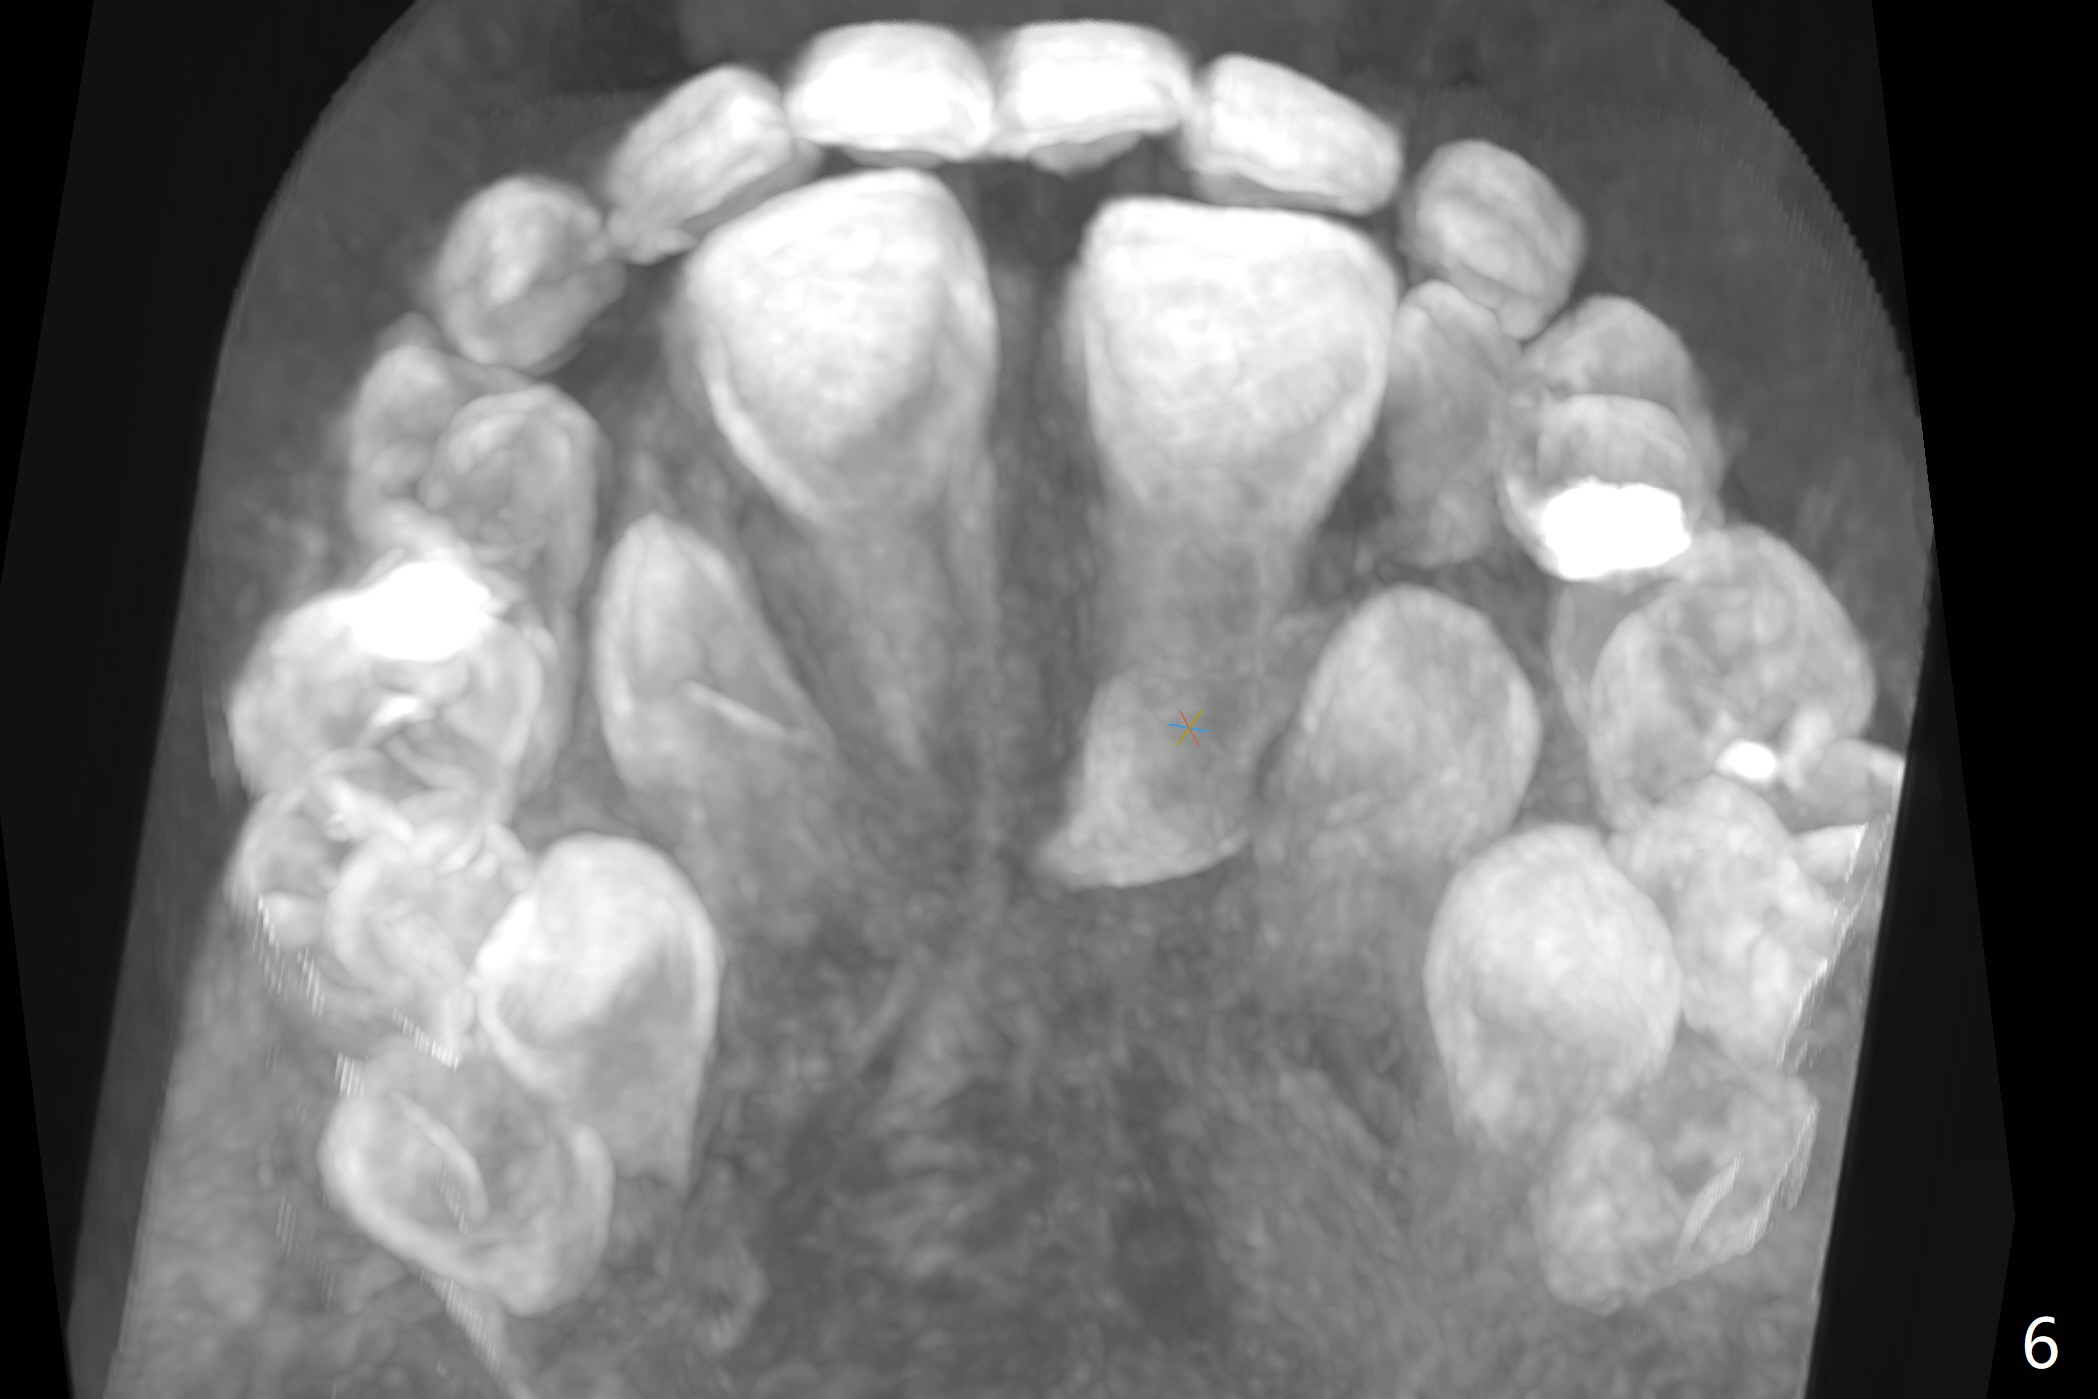

The father of a 7-year-old boy wonders why the upper central incisors, particularly #9, are off (Fig.1 3-D CT tooth coloring). Fig.2 (bone coloring) does not reveal much. Fig.3 (MIP, more transparent) reveals a supernumerary tooth, called mesiodens (M, an extra central incisor, abnormally shaped (cone), near the midline). Palatal view shows that the mesiodens points to the midline and distal (arrow). A palatal gingival sulcus incision will be made to expose the extra tooth (Fig.5). An elevator will be used as midline and distal as possible to avoid damage to the root of #9 and the tooth bud of #10 (Fig.6 MIP). Photos will be taken frontally and palatally preop and after incision and exposure of the mesiodens (palatal).

There is a large diastema between the upper central incisors (Fig.7). The left anterior palate is slightly elevated (Fig.8 *). In fact the cortex overlying the mesiodens (Fig. 9 *, 11 <) is to be removed with a surgical handpiece in order to extract the mesiodens (Fig.10). The left central shifts mesial in 7.5 months postop, whereas the right one remains in place (Fig.12). The tooth #7 is unerupted 1 year 4 months postop (Fig.13).